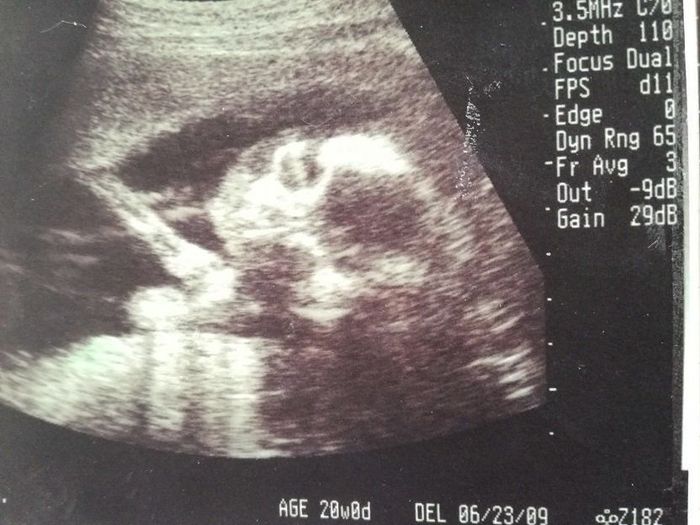

妊娠20週目のエコー写真

前回と今回の妊婦検診の間に、実は子宮の硬直と出血を起こして、自宅で安静している期間がありました。その間は、おなかの痛みと、絶え間なく頭に浮かぶ不安に耐える日々…。そのため、このエコー画像で元気な赤ちゃんの姿を確認した時は、体の奥が温かくなったのを記憶しています。顔に手を添える様子がほほ笑ましく、おなかを触りながら何度も見返しました。先生から「無理しない程度に、通常の生活に戻っていいよ」と言われました。